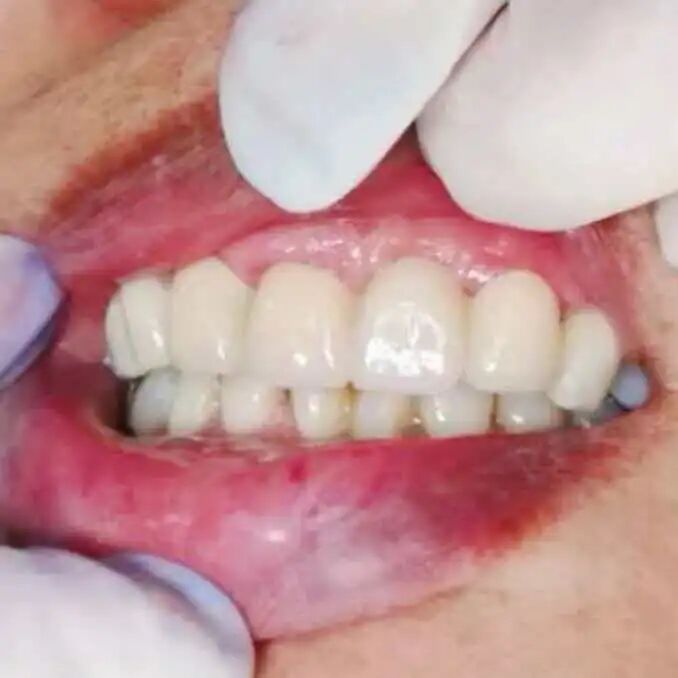

医生将修复方案和注意事项告知小美和家属后,他们表示理解并同意进行全冠修复。经过牙体预备、模型制取、临时冠佩戴等步骤,一周后,制作好的全瓷牙冠被戴入小美的口内。

戴上牙冠后,小美在镜前仔细端详,修复后的牙齿在颜色和形态上与邻牙协调一致,看起来自然。她露出了满意的笑容,之前的疼痛和担忧也随之消散。